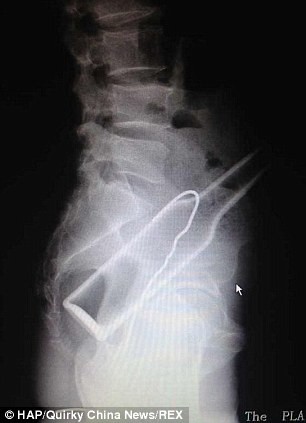

Un hombre que se introdujo una botella en el recto, debió pedir ayuda médica luego de intentar solucionar el problema por su cuenta. Para ello, trató de "pescar" el envase con un gancho de alambre, pero segundo objeto también quedó atrapado dentro de sus intestinos.

El individuo, según consigna MailOnline, acudió a un hospital de la ciudad de Fuzhou, quejándose de dolores de vientre. Ante la evidencia, confesó que se había introducido la botella, y que luego, asustado, había maniobrado sin éxito con el gancho.

Los médicos debieron recurrir a la cirugía para extraer ambos objetos, y durante el procedimiento descubrieron que el intestino grueso del paciente había recibido rasguños en varias partes, causados por el gancho de metal.